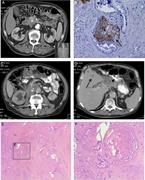

Back pain as a potential indicator of local recurrence in pancreatic cancer

Elke Tieftrunk and others

Journal of Surgical Case Reports, Volume 2015, Issue 10, October 2015, rjv127, https://doi.org/10.1093/jscr/rjv127